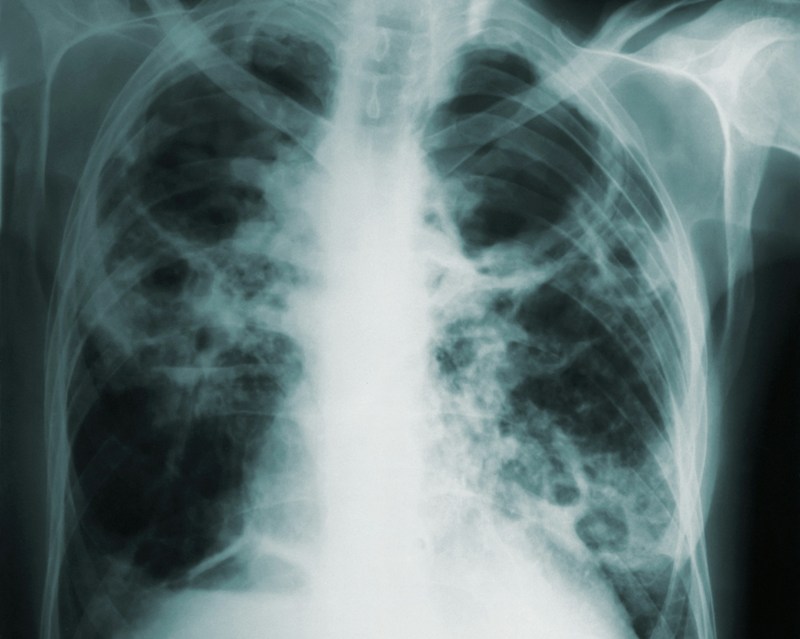

TB

New WHO report shows TB has overtaken COVID-19 as leading infectious disease killer in 2023

The World Health Organization (WHO) on Tuesday published a new report on tuberculosis revealing that approximately 8.2 million people were newly diagnosed with TB in 2023 – the highest number recorded since WHO began global TB monitoring in 1995.

This represents a notable increase from 7.5 million reported in 2022, placing TB again as the leading infectious disease killer in 2023, surpassing COVID-19.